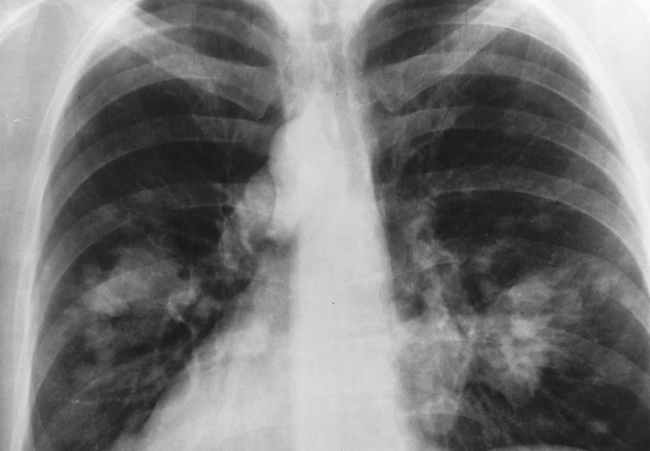

lung x-ray

Successful patient outcome in lung cancer clinical trial

July 9, 2018